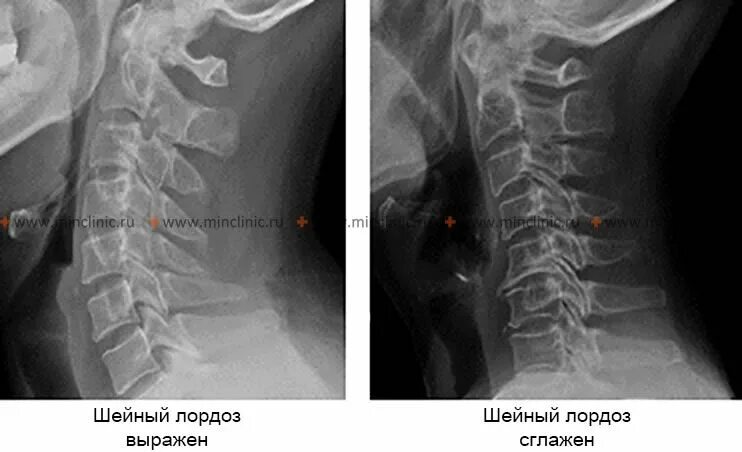

Как исправить шейный отдел